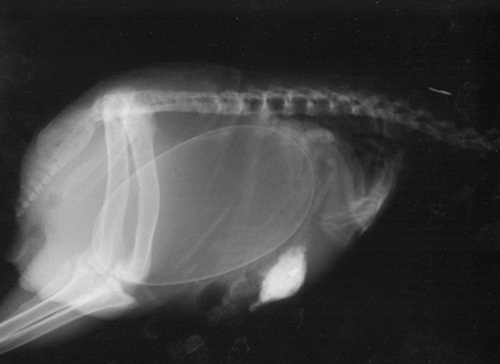

Bào thai chó.

Bào thai mèo.